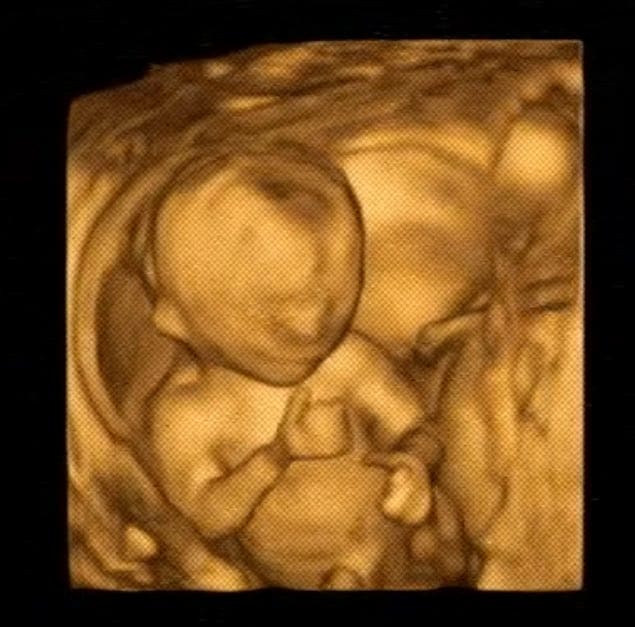

「こんなこっち向いてファンサしてくれる事ある?よく見たらグッジョブしてるし お前…さては陽キャだな?」そんなコメントとともに投稿されたのは、1枚の写真でした。

写真には、@58vfw214さんが妊婦健診の胎内エコーで見た光景が収められていました。お腹にいる赤ちゃんはこちらを向いているようで、よく見ると「グッジョブ」のポーズを見せてくれています。

さらには笑顔を浮かべているようなお顔も印象的。なんとも愛らしい光景に、自然とホッコリした気持ちになりますね。

@58vfw214さんに話を聞くと「今回3人目の妊娠ですが、こんなにハッキリと正面でエコーを見れたのは初めてだったのでビックリしました(笑)」と振り返ります。